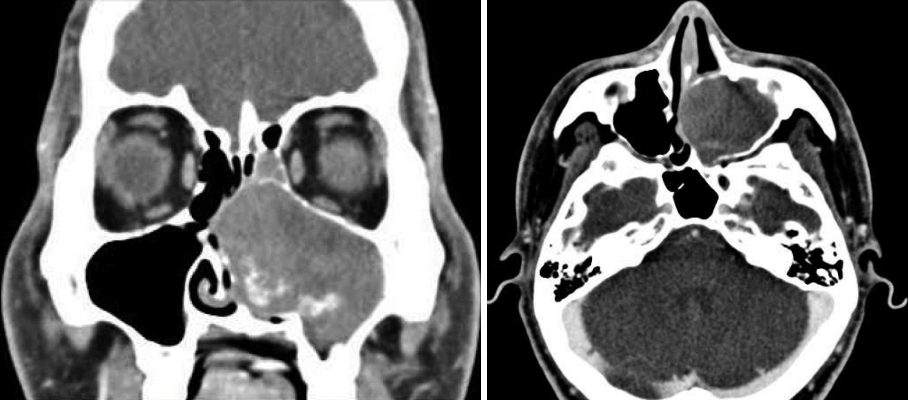

22세 남자가 내원 1년 전부터 심화되는 좌측 코막힘을 주소로 내원하였다. 환자는 1년 전 만성비염으로 개인병원에서 코블레이터를 이용한 하비갑개 성형술을 시행받았으며 수술 이후 좌측 비폐색이 점차 심해져 추가적인 검사 및 치료를 위해 본원을 방문하였다. 과거력상 비염 외 특이질환은 없었고 이전의 안면 및 부비동의 수술이나 외상의 과거력은 없었다. 또한 가족력상에서도 특이사항은 없었으며, 일반 혈액검사 및 일반 화학검사, 혈청검사 및 혈액응고검사상에서도 특이소견은 보이지 않았다. 비강 내시경 소견상 좌측 하비갑개 전방부에 코블레이터 삽입 위치로 보이는 반흔조직이 관찰되었으며 하비갑개 후방부의 비후소견이 관찰되었고 비후조직으로 인해 중비도 및 후비강의 확인은 불가능하였다(Fig. 1). 우측 비강은 심한 비중격의 우측편위 소견을 보였고 종물 등의 특이소견은 보이지 않았으며 비인두에도 특이소견은 관찰되지 않았다. 조영제를 사용한 부비동 전산화단층촬영에서 좌측 상악동을 가득 채운 균일하지 않게 조영 증강된 종괴가 관찰되었으며 종괴는 상악동 내측벽을 밀어내며 팽창하는 양상을 보였다(Fig. 2). 좌측 전사골동부 일부에 부비동염 소견 외 나머지 부비동에 이상소견은 보이지 않았으며 안와저골부의 침범소견도 관찰되지 않았으나 팽창성 종괴에 의해 비중격이 반대편으로 밀리는 소견이 관찰되었다. 혈관종이나 반전형 유두종 및 신경섬유종, 기질화 혈종 등이 의심되어 진단 및 치료를 위해 전신마취 하에 내시경적 접근을 통한 종괴의 절제술을 계획하였다. 수술 시 비강을 통해 내시경 접근법으로 종괴의 변연을 확인하였고 좌측 상악동의 내측 후방 기원의 종괴임을 확인한 뒤 회전절삭기 및 소작기를 사용하여 종괴를 조각 내어 제거하였다. 혈종 발생부위는 상악동 내측 후방부였으며 박리과정에서 접형구개동맥의 분지로 추정되는 동맥의 출혈이 발생하여 흡입기가 연결된 단극성 소작기를 통해 출혈을 조절하였다. 배출된 종괴의 내부는 혈관이 잘 발달되어 있었고 섬유화가 진행되어 단단한 질감이었으며 종괴의 외측부에는 점액성 액체가 포함된 점액낭종이 일부 관찰되었다(Fig. 3). 술 후 병리조직학적 소견에서 종괴는 내부에 풍부한 신생혈관들과 섬유화가 관찰되어 기질화 혈종으로 진단되었다(Fig. 4). 수술 이후 환자의 코막힘 증상은 사라졌으며 6개월간 추적관찰을 한 결과 종괴의 재발소견은 보이지 않았고 부비동 전산화단층촬영상 비중격의 우측 편위도 다소 정상으로 돌아온 것이 확인되었다(Fig. 5).